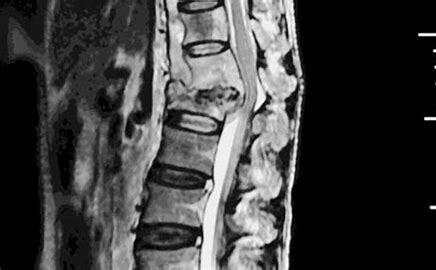

经过诊断,王家红确诊脊柱结核、耐多药肺结核等多器官结核。因结核杆菌侵蚀破坏胸椎骨质、脊髓受压引起下肢瘫痪,她出现了下肢肌力丧失,小便失禁等症状。于是,20岁的李丽云每个月都会背着瘫痪的妈妈来长沙市中心医院耐药结核科复查。

“脊柱结核是一种继发性病变,常继发于肺结核、消化道结核及淋巴结核等,好发于人体的脊柱。椎体病变不仅会造成骨质破坏及坏死,还可能造成椎体塌陷,使脊柱形成弯度,棘突隆起,此症状在胸椎结核里表现得尤为明显。一旦椎体塌陷,死骨,就可使脊髓受压,甚至可至截瘫。”该院耐药结核科主任裴异介绍:“王家红不知道自己感染了耐药性肺结核,未及时就医,在身体抵抗力下降的情况下又继发了胸椎结核,引发了下肢瘫痪。”